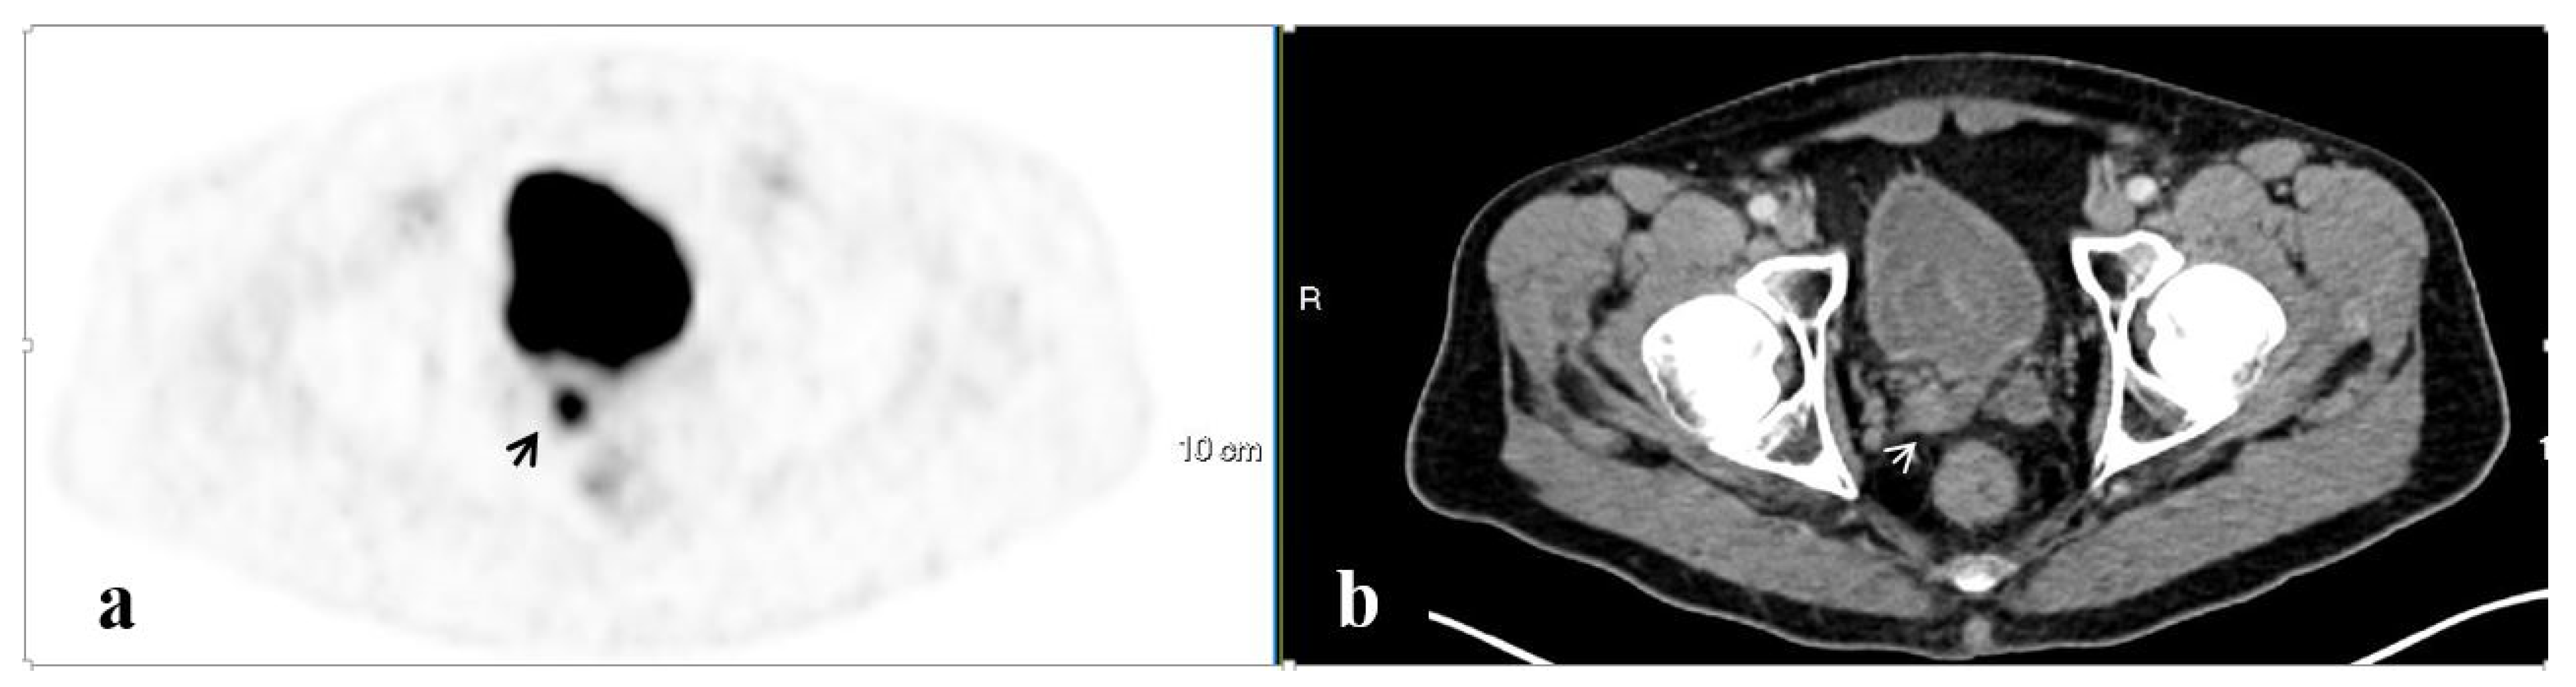

| Site | No. of Men | Mean SUVmax 1 | Mean Lesion Size (mm) 1 | No. Accompanied by LN |

|---|---|---|---|---|

| Isolated pelvic LAD | 43 | 11.0 ± 11.5 | 1.0 ± 0.3 | n/a |

| Prostate | 37 | 10.0 ± 6.4 | 2.1 ± 1.1 | 11 |

| SV | 23 | 8.6 ± 5.9 | 0.5 ± 0.5 | 7 |

| Pelvic bones | 16 | 14.2 ± 18.2 | 2.0 ± 1.0 | 2 |

| PF | 7 | 5.8 ± 5.6 | 1.4 ± 0.4 | 2 |

| SVF | 3 | 6.0 ± 1.6 | 1.3 ± 0.4 | 1 |

| Other 2 | 6 | 8.0 ± 3.2 | 1.3 ± 0.4 | 2 |